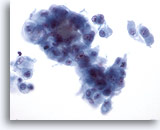

Lymph node FNA, reactive lymphoid hyperplasia. A FNA of a lymph node may yield small irregular clusters of macrophages and lymphocytes. These should not be misinterpreted as an epithelial neoplasm. There are two such clusters here along with many other small round cells of varying sizes. 20x

Lymph node FNA, reactive lymphoid hyperplasia.

A FNA of a lymph node may yield small irregular clusters of macrophages and lymphocytes. These should not be misinterpreted as an epithelial neoplasm. There are two such clusters here along with many other small round cells of varying sizes.

20x